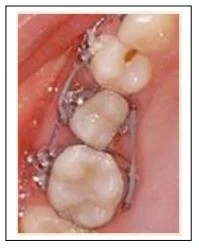

1.1. Chun tách khe:

Rẻ và rất dễ sử dụng ở trẻ em và thanh niên. Ở những điểm tiếp xúc chật, có chứa miếng trám bạc amalgam, thì chun tách khe dễ bị đứt lúc đưa quá điểm tiếp xúc. Có vẻ như chúng cản trở khớp cắn, không cho phép bệnh nhân cắn chặt hai hàm lại với nhau. Do cản trở khớp cắn như vậy cộng với lực mạnh từ vật liệu Polyurethane đặt vào răng gây ra những cảm nhận đầu tiên về lực, rất nhiều bệnh nhân sẽ than phiền vì đau. Vì lý do này chúng ta thường không sử dụng chun tách khe ở người lớn, những đối tượng nhậy cảm với đau cản trở khớp cắn hơn.

1.2. Lò xo Ni-ti

Lò xo Ni-ti dễ đặt vào mọi điểm tiếp xúc, giải phóng lực nhẹ, tự đứng tại chỗ và không cản trở khớp cắn, Lò xo đắt tiền hơn, tuy nhiên bạn có thể hấp và tái sử dụng, giảm chi phí xuống một nửa mỗi lần bạn đặt thêm.

Lò xo Ni-ti có thể mở đủ khoảng tiếp xúc để di chuyển sâu hơn về phía mô mềm. Phải chắc chắn luôn luôn đếm lò xo khi lấy bỏ nó. Bất cứ khi nào không thấy đủ thì phải tìm ở dưới mô lợi.

Chân đứng của lò xo có thể in dấu trên mô lợi trong trường hợp mô lợi này có thân răng lâm sàng ngắn. Có thể cắt ngắn chân lò xo Niti được bằng kìm cắt pin/ligature. Luôn kiểm tra để chắc chắn chân đứng của lò xo nằm ôm lấy cấu trúc răng và không kẹp vào mô lợi.